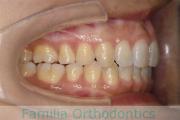

歯並びを治したいということで来院されました。下あごがやや右側に偏位して後退している、上顎前突(出っ歯)でした。上下左右から小臼歯を抜歯して、歯科矯正用アンカースクリューを併用したマルチブラケット法にて治療を行いました。約2年、24回の来院をしていただきました。

下顎の後退はいびきなどの上部気道の障害が出やすいと考えられます。